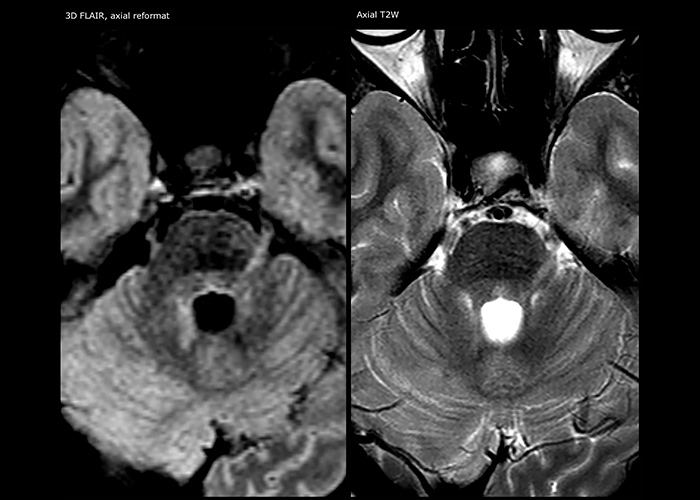

“Ingenia 3.0T provides us very good image quality with high SNR, even if we push the resolution. For example, in FLAIR images we may have an isotropic resolution of 0.9 mm. Ingenia allows us to use 3D T1 TSE with BrainView, which has a better sensitivity than 2D spin echo imaging[2] and 3D gradient echo imaging. Ingenia also provides highly reproducible exams, which is important in MS imaging so that follow-up exams at different time points are done the same way.”

For MS imaging in the brain, Dr. Savatovsky uses 3D FLAIR as the basic sequence to visualize the lesions and assess the situation and lesion load. “We count the lesions in each location to determine if the criteria of the disease are fulfilled. We use a T2-weighted sequence because our neurologists are used to it. We compare the lesion load on FLAIR with a 3D T1 post-contrast sequence to help us determine whether lesions are old or new. We typically administer the contrast before the patient enters the machine because it shortens the examination time and allows to visualize active lesions that tend to be more visible after several minutes. When a differential diagnosis is difficult, we add sequences such as susceptibility imaging, because some focal MS lesions have a small vein in the center[3].”